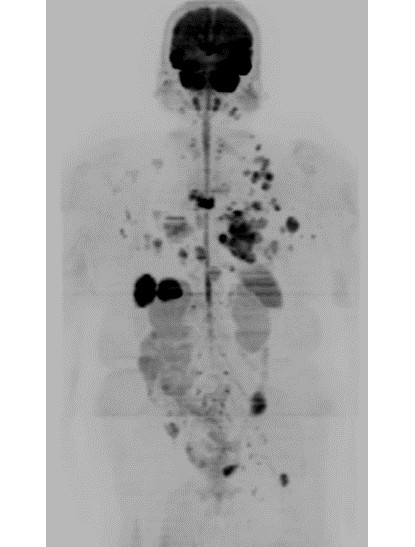

症例1:左乳癌術後経過観察(60代女性)

PET/CTではFDGの生理的集積のある膀胱も描出されている。

DWIBSでは正常な膀胱は描出されず、膀胱内や膀胱周囲の病変検出が可能。